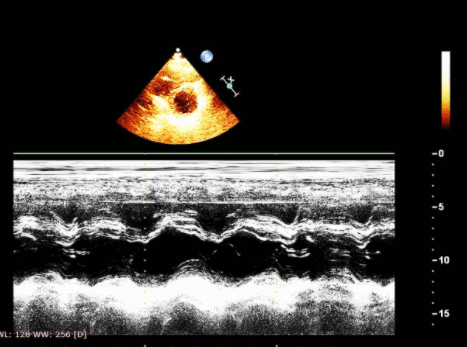

Во время эхокардиоскопии доктор использует различные режимы УЗ аппарата:

- одномерный (М-режим),